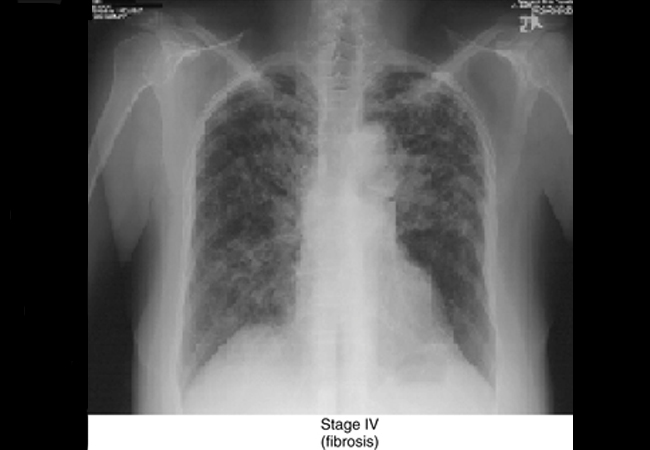

Zdjęcie rentgenowskie przedstawiające włóknienie płuc w przebiegu sarkoidozy

• zdjęcie rentgenowskie klatki piersiowej – pozwala wykryć zmiany w płucach lub węzłach chłonnych